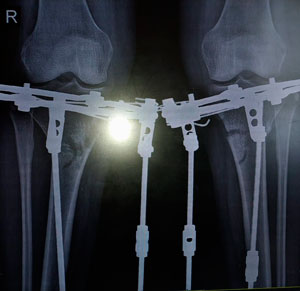

Дата операции - 04.07.2019г.

Дата снятия аппаратов - 10.10.2019г.

Срок сращения - 95 дней.